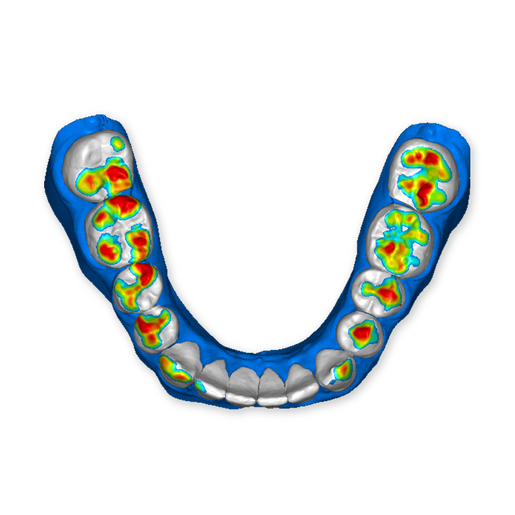

The DSD Interdisciplinary is a digital wax up of the upper and lower arches, designed considering a facially-driven, clinical and functional analysis of the patient.

It is our most comprehensive planning option, and includes all the 3D treatment simulations needed for each case, such as ortho, perio, implants, grafts and orthognathic surgery.

Our 3D simulations showcase facilitate a deeper understanding of the required procedures. This leads to the creation of a broader treatment plan and enables a more efficient communication with your patients.